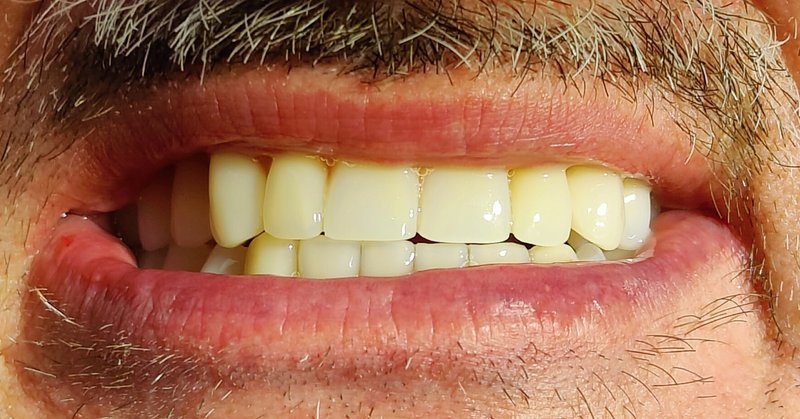

Fast zahnlos über Jahre: Drei Kronen mit Lokatorenspitzen.

Praktische Zahnlosigkeit über Jahre - Erschwerte Therapie durch Makroglossie

Ein Fallbericht von Daniel Liss – Zahnarzt im AllDent Zahnzentrum Leipzig

Der Fall zeigt, dass auch unter widrigen Umständen (lange Zahnlosigkeit, Makroglossie) Full-Arch-Sofortversorgungen auf vier Implantaten möglich sind. Trotz oder möglicherweise gerade wegen der langen Zahnlosigkeit war der Patient bereits mit den provisorischen Brücken sehr gut zurechtgekommen. Durch die Perfektionierung des Bisses konnten Freude und Zufriedenheit über die neuen Zähne noch gesteigert werden. Auch das Behandlungsteam durfte sich schließlich über die erfolgreiche Bissrehabilitation und das Einhalten der guten medizinischen Standards freuen.